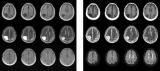

便携式MRI能以极低的成本实现对脑部疾病的检测

核磁共振成像(MRI)是一个强大的诊断工具,但机器的尺寸和成本却限制了它的使用范围。来自中国香港大学的科学家们现在已经开发出一种更紧凑、更实惠的MRI系统,它使用的磁场更小且不需要屏蔽,同时仍能对病人的大脑疾病展开诊断。 2021-12-15 PET/MRI磁共振成像